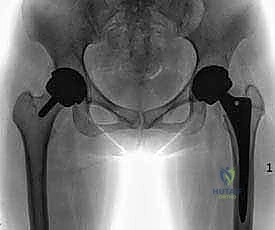

على عكس عملية "الاستبدال الكامل لمفصل الورك" (Total Hip Replacement - THR) التي يتم فيها قطع وإزالة رأس عظمة الفخذ بالكامل مع جزء من عنق العظمة لزرع جذع معدني طويل داخل التجويف العظمي، فإن تقنية استبدال السطح تقوم فقط بإزالة الغضروف المتآكل والطبقة السطحية التالفة من العظم. بعد ذلك، يتم "تغليف" أو "تلبيس" رأس عظمة الفخذ الطبيعي بغطاء معدني أملس (يشبه التاج الذي يوضع على السن التالف)، ويتم وضع قبة معدنية أخرى داخل تجويف الحُق (Socket) في الحوض.

| وجه المقارنة | استبدال سطح مفصل الورك (Hip Resurfacing) | الاستبدال الكامل لمفصل الورك (Total Hip Replacement) |

| الهدف الأساسي | الحفاظ على عظم الفخذ الأصلي وتلبيسه بمعدن. | إزالة رأس وعنق عظمة الفخذ بالكامل واستبدالها. |

| الفئة العمرية المفضلة | الشباب والبالغين النشطين (عادة تحت 60 عاماً). | كبار السن أو من يعانون من هشاشة عظام متقدمة. |

| خطر خلع المفصل | منخفض جداً (لأن حجم المفصل يطابق الطبيعي). | أعلى نسبياً (يتطلب حذراً في بعض الحركات). |

| النشاط الرياضي بعد التعافي | يسمح بالعودة للرياضات عالية التأثير (الجري، فنون القتال). | يقتصر غالباً على الرياضات خفيفة التأثير (المشي، السباحة). |

| خيارات الجراحة المستقبلية | ممتازة (يمكن تحويله لاحقاً لاستبدال كامل بسهولة). | محدودة (الجراحات المراجعة أكثر تعقيداً). |

| قوة العظام المطلوبة | يتطلب عظام فخذ قوية وسليمة لتحمل الغطاء المعدني. | يمكن إجراؤه حتى مع وجود هشاشة عظام. |